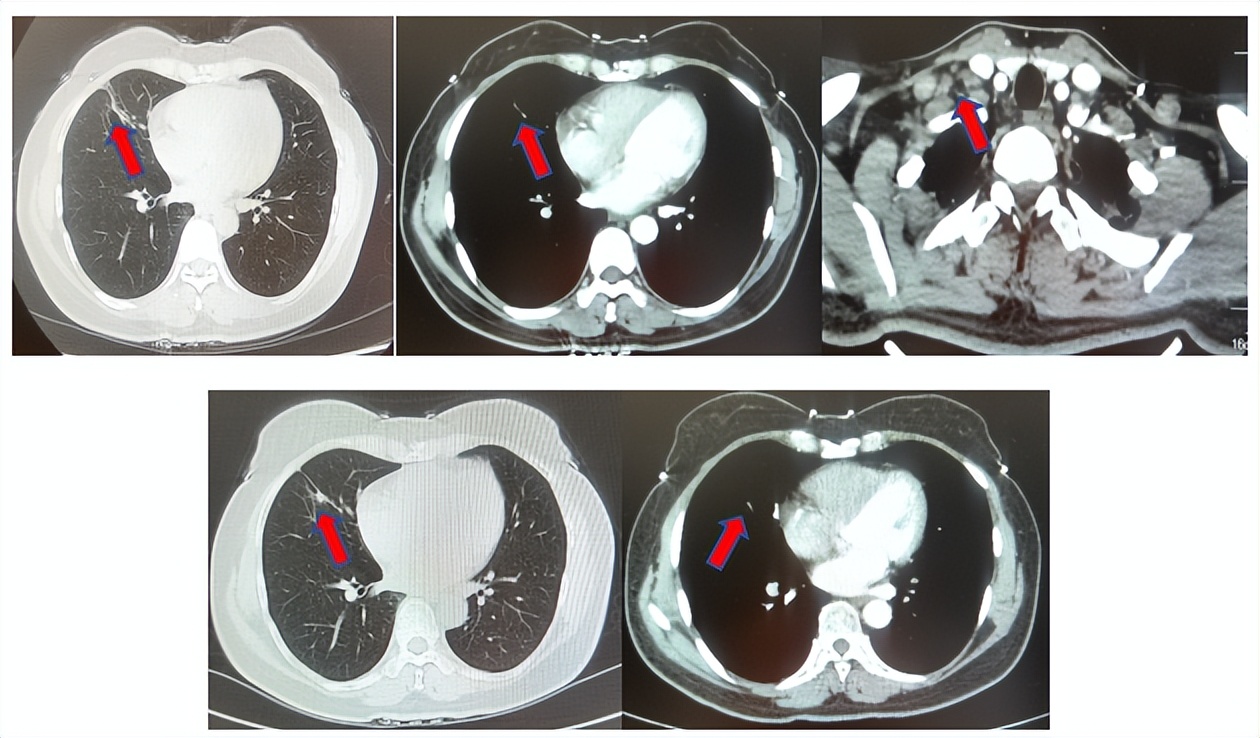

2.2影像学检查(图5)

肺+全腹CT增强:右肺中叶肿块,考虑恶性,双肺胸膜下炎症,双侧胸膜局限性增厚,右侧锁骨上淋巴结增大,纵隔淋巴结稍大;

颈部CT增强:右侧锁骨上及右颈部、纵隔多发淋巴结肿大。

图5:上两图分别展示基线时肺CT肺窗及纵隔窗右肺中叶病灶影像,下两图表示基线状态时纵隔淋巴结及锁骨上淋巴结影像。

患者符合我科正在开展的一项“评估信迪利单抗或安慰剂联合培美曲塞和铂类化疗用于晚期或复发性肺鳞状细胞非小细胞肺癌一线治疗有效性和安全性的随机,双盲,III期研究(ORIENT-11)”临床研究入组条件,应用信迪利单抗或安慰剂联合培美曲塞+卡铂治疗4周期,信迪利单抗或安慰剂联合培美曲塞维持治疗13周期,后应用信迪利单抗或安慰剂应用至2年。试验结束后出组,揭盲患者为信迪利治疗组。治疗期间最佳疗效肺内病灶近CR(图6)。停药后每3个月-6个月复查随访,未见肿瘤复发转移征象(图6),截止至目前为止,一线无进展生存已超过75个月。

图6:上三图分别展示2019年6月患者达到最佳疗效时肺CT肺窗及纵隔窗右肺中叶病灶及锁骨上淋巴结影像,下两图表示2025年2月患者最近复查评效时肺CT肺窗及纵隔窗肺内病灶影像